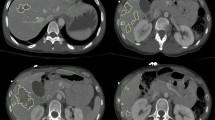

Our pipeline includes 4 parts: (1) automated splenic localization, (2) Faster R-CNN-based detection of pseudoaneurysms (PSA) and active bleeds (AB), (3) nnU-Net segmentation and quantification of splenic parenchymal disruption (SPD), and (4) a directed graph that infers AAST grades from detection and segmentation results. Training and validation is performed on a dataset of adult patients (age ≥ 18) with voxelwise labeling, consensus AAST grading, and hemorrhage-related outcome data (n = 174).

AAST classification agreement (weighted κ) between automated and consensus AAST grades was substantial (0.79). High-grade (IV and V) injuries were predicted with accuracy, positive predictive value, and negative predictive value of 92%, 95%, and 89%. The area under the curve for predicting hemorrhage control intervention was comparable between expert consensus and automated AAST grading (0.83 vs 0.88). The mean combined inference time for the pipeline was 96.9 s.